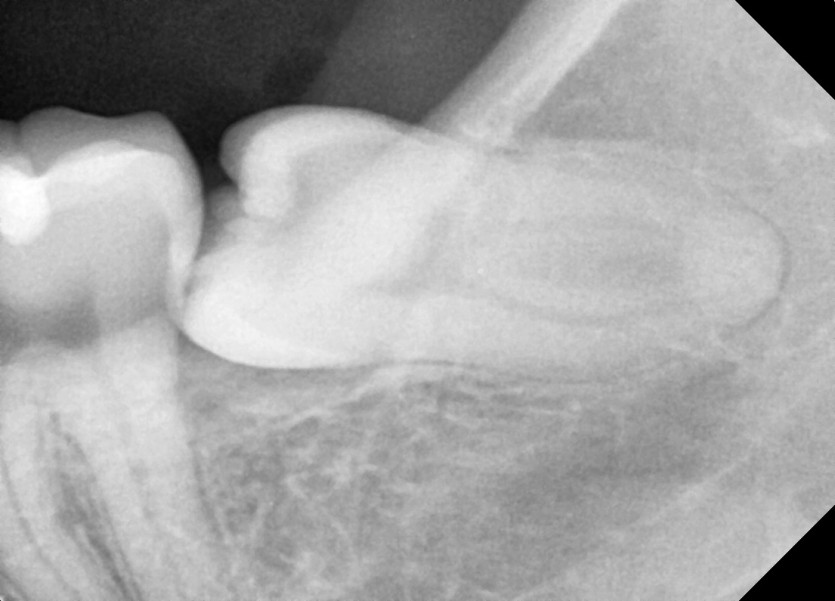

#38 사랑니 발치

구강 외과 전문의가 당일 발치했습니다.